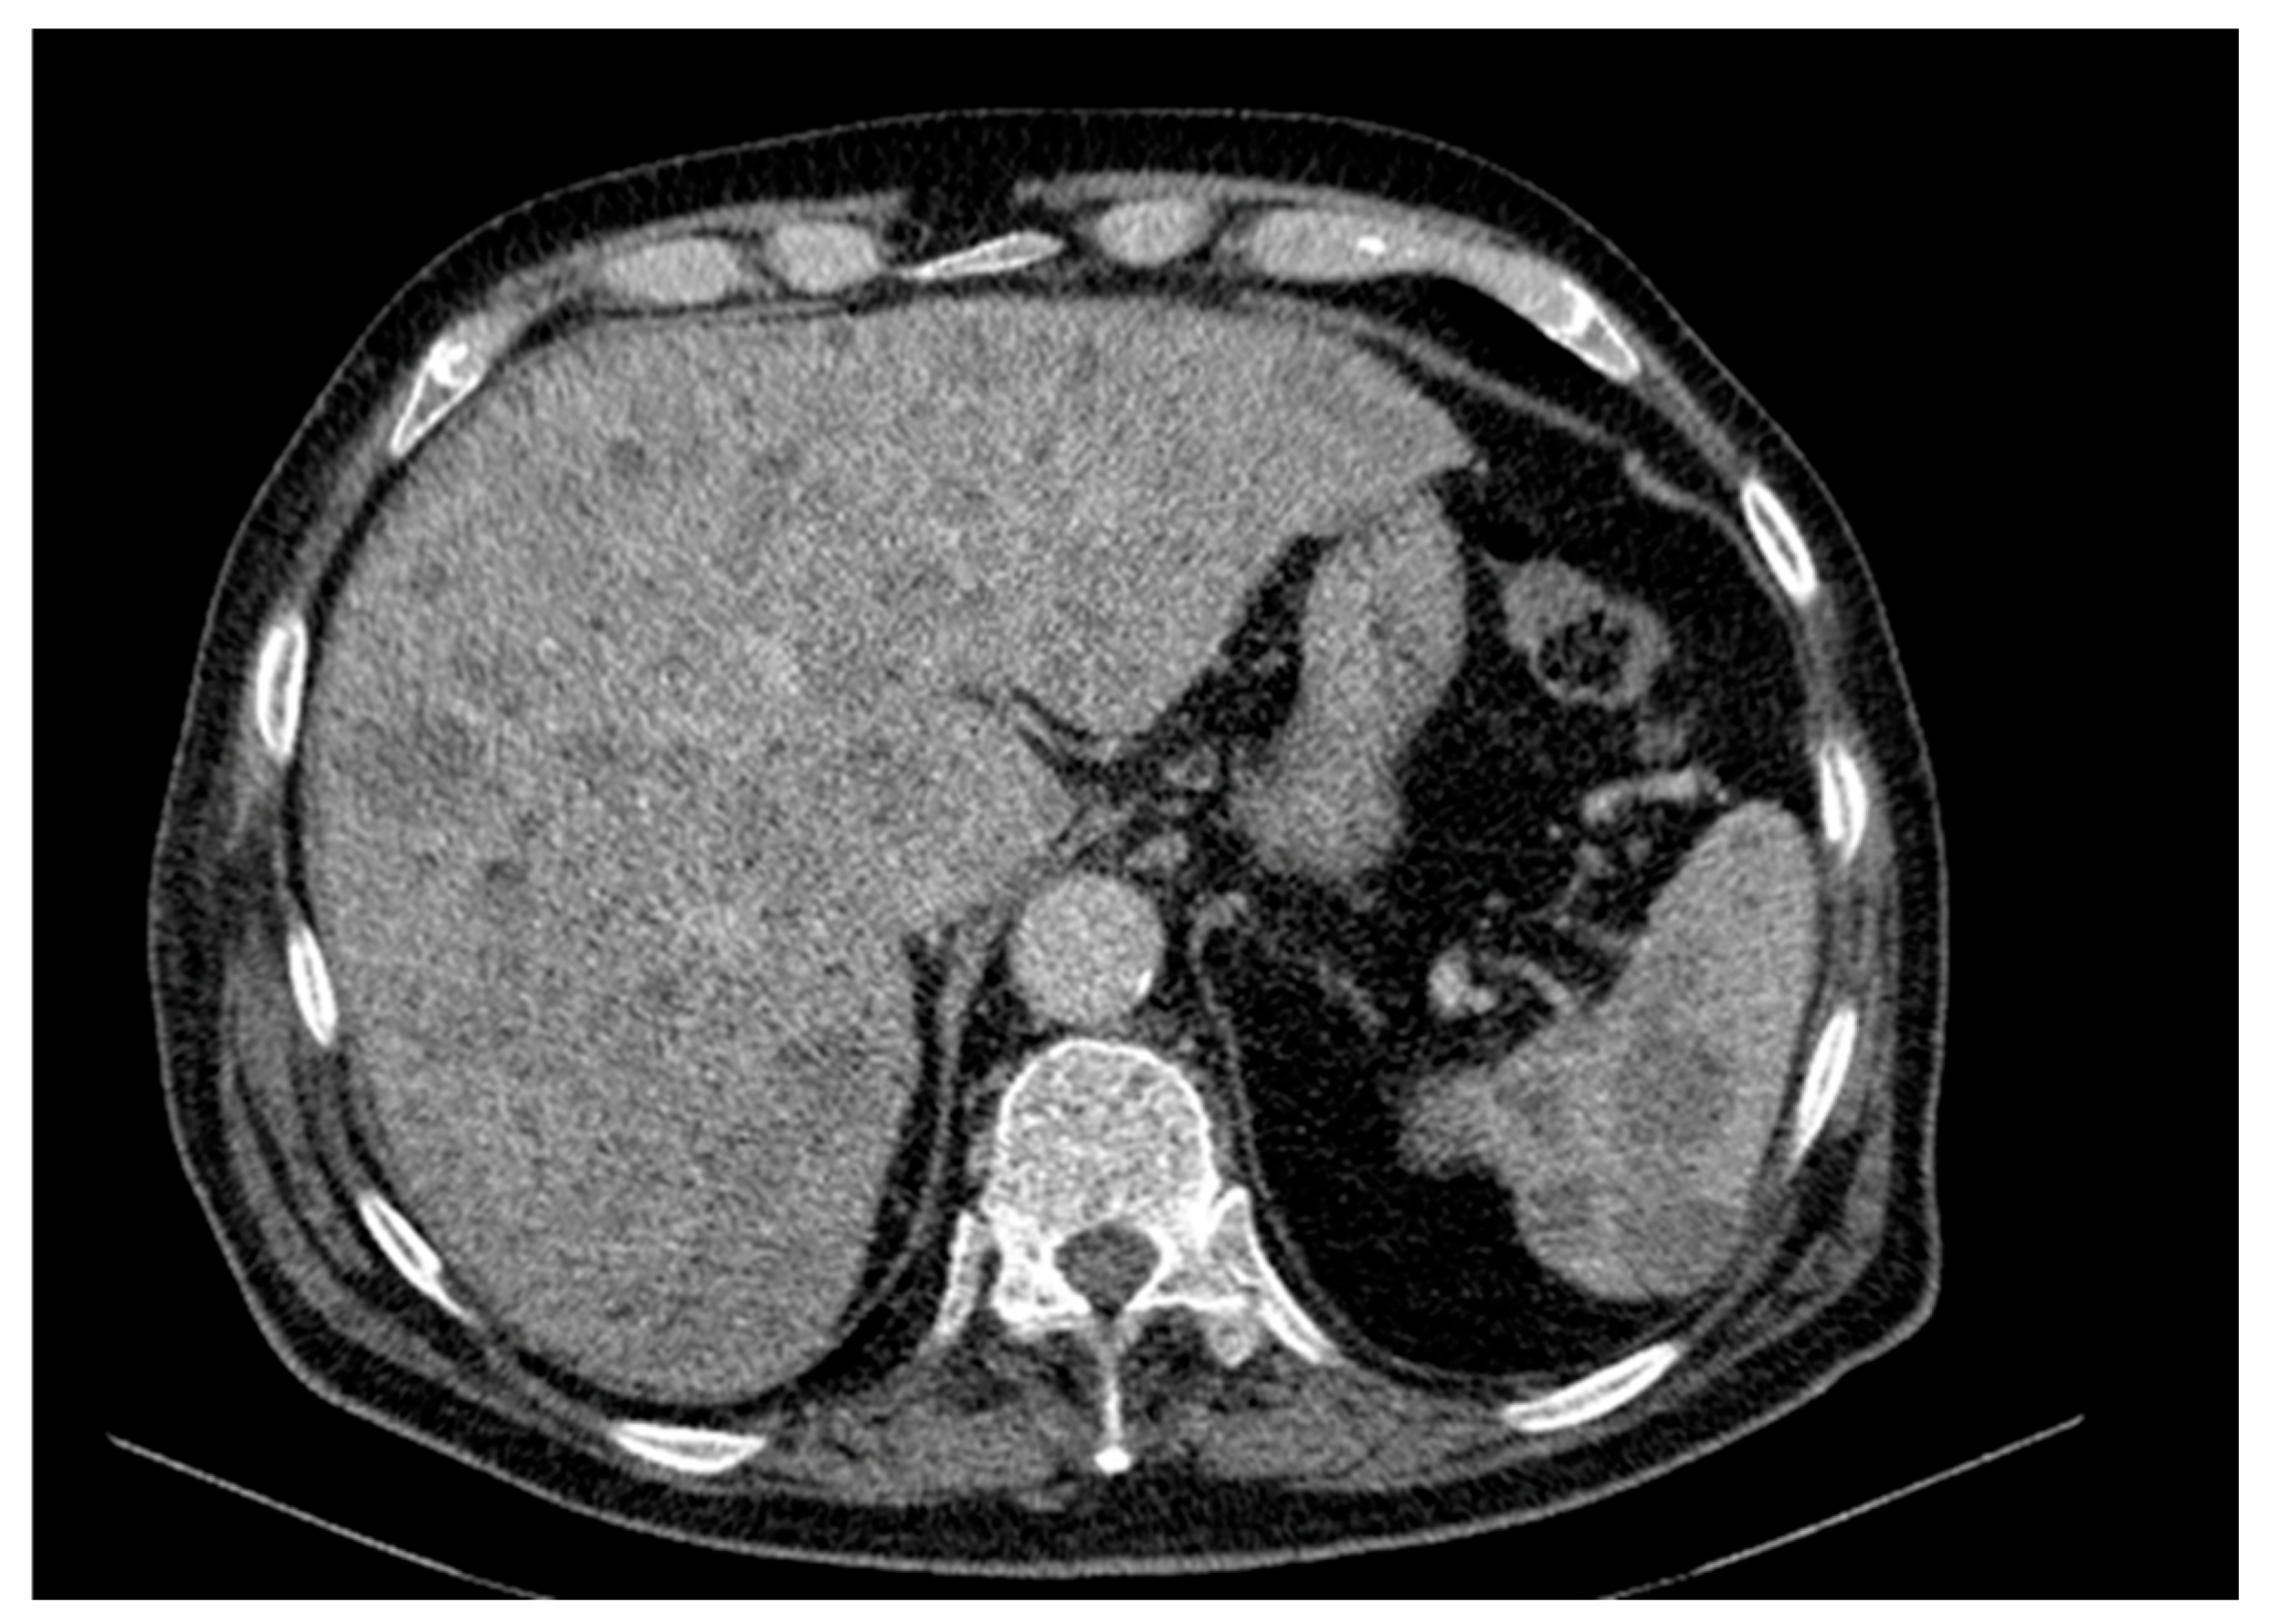

Abdominal and pelvic CT revealed hepatosplenomegaly with multiple hypodense, non-enhancing nodular lesions, precaval and hilar lymphadenopathy, bilateral renal cysts (up to 50 mm on the right), a right renal pelvis stone, a right ureteral stent and diffuse osteoporotic changes with vertebral L1 collapse and hyperdense nodular lesions suggestive of possible bone metastases (Figure 3).

Figure 3. Contrast-enhanced abdominal and pelvic CT scan revealing hepatosplenomegaly with multiple hypodense, non-enhancing nodular lesions suggestive of secondary involvement. Bilateral renal cysts, more numerous and larger on the right (up to 50 mm), a 9 mm right renal pelvis stone, and the presence of a right ureteral stent are noted. Diffuse bone structure changes with osteoporotic background and poorly defined hyperdensities are seen, along with L1 vertebral body collapse.